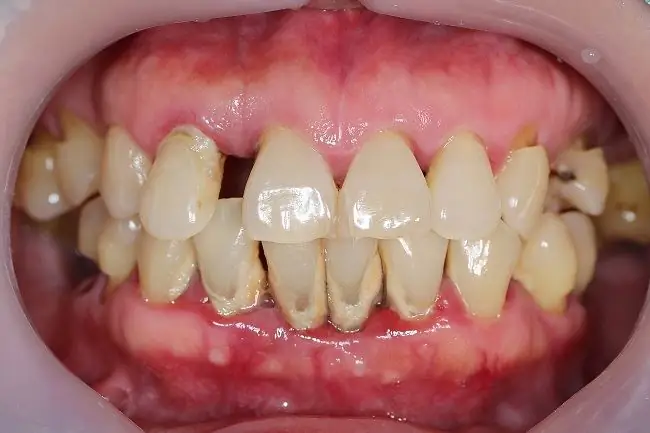

Симптомы пародонтита

Симптомы пародонтита могут различаться и зависят от развития воспаления, возникающего в деснах и зубах. Тем не менее, есть некоторые симптомы или жалобы, которые обычно возникают у людей с пародонтитом, а именно:

• Боль при жевании

• Налет и зубной камень на зубах

• Расстояние между одним зубом и другим кажется незначительным

• Уменьшает десны, делая зубы длиннее

• Красные или пурпурные десны

• Десны болезненны на ощупь

• Опухание десен и легкое кровотечение

• Точь выделения из зубов и десен

• Зубы шатаются или дата

• Чувствительные зубы

• Неприятный запах изо рта